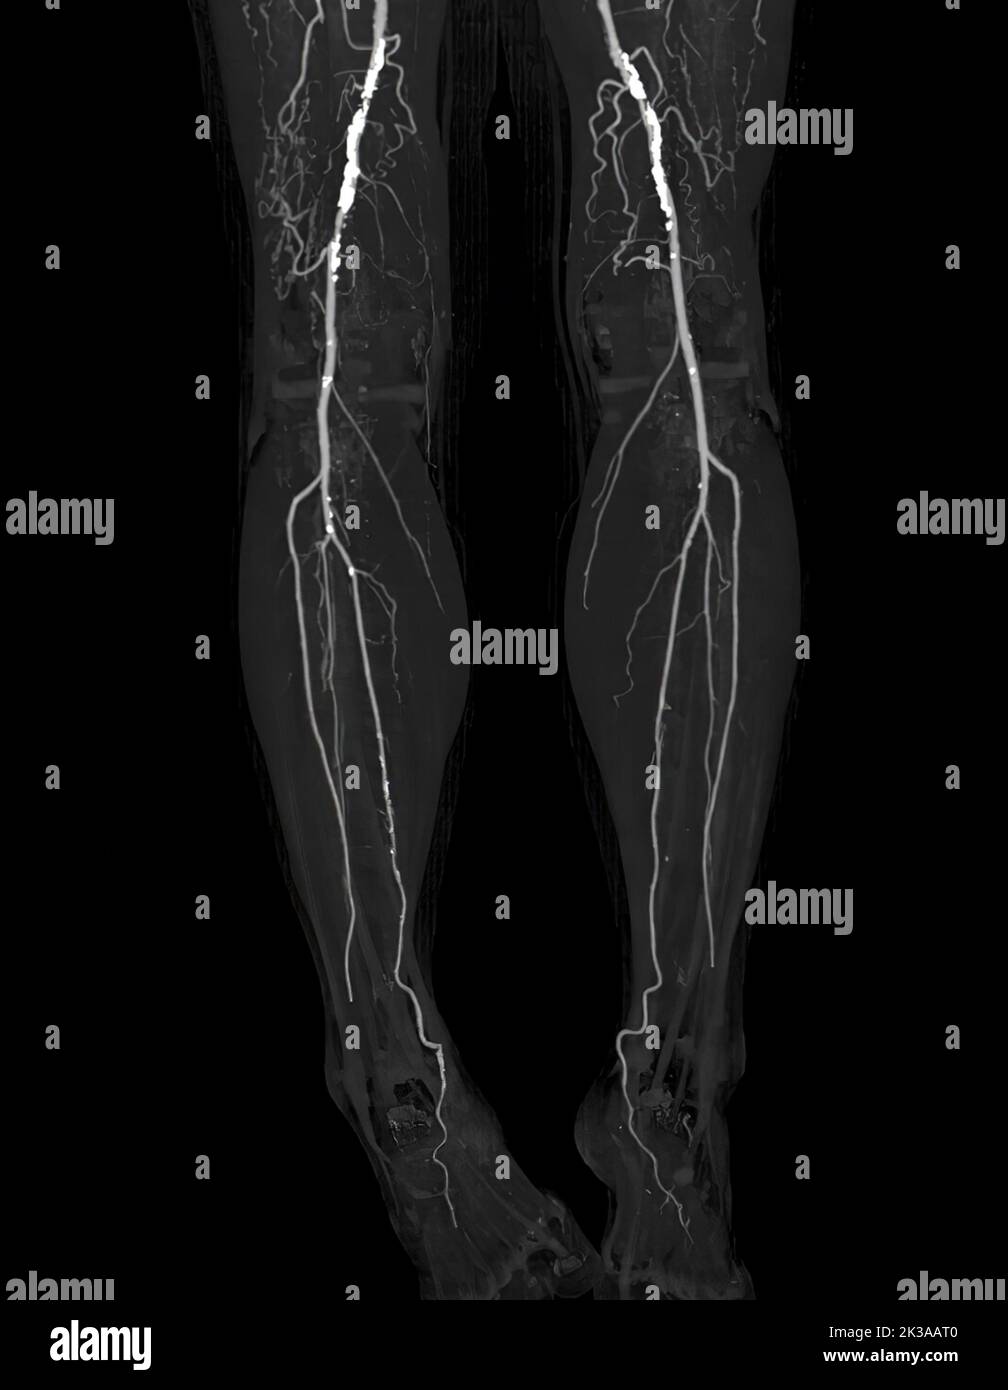

CTA femoral artery run off image of femoral artery Presenting with Acute or Chronic Peripheral Arterial Disease. Stock Photohttps://www.alamy.com/image-license-details/?v=1https://www.alamy.com/cta-femoral-artery-run-off-image-of-femoral-artery-presenting-with-acute-or-chronic-peripheral-arterial-disease-image483964086.html

CTA femoral artery run off image of femoral artery Presenting with Acute or Chronic Peripheral Arterial Disease. Stock Photohttps://www.alamy.com/image-license-details/?v=1https://www.alamy.com/cta-femoral-artery-run-off-image-of-femoral-artery-presenting-with-acute-or-chronic-peripheral-arterial-disease-image483964086.htmlRF2K3AD3J–CTA femoral artery run off image of femoral artery Presenting with Acute or Chronic Peripheral Arterial Disease.

CTA femoral artery run off image of femoral artery Presenting with Acute or Chronic Peripheral Arterial Disease. Stock Photohttps://www.alamy.com/image-license-details/?v=1https://www.alamy.com/cta-femoral-artery-run-off-image-of-femoral-artery-presenting-with-acute-or-chronic-peripheral-arterial-disease-image483962304.html

CTA femoral artery run off image of femoral artery Presenting with Acute or Chronic Peripheral Arterial Disease. Stock Photohttps://www.alamy.com/image-license-details/?v=1https://www.alamy.com/cta-femoral-artery-run-off-image-of-femoral-artery-presenting-with-acute-or-chronic-peripheral-arterial-disease-image483962304.htmlRF2K3AAT0–CTA femoral artery run off image of femoral artery Presenting with Acute or Chronic Peripheral Arterial Disease.

CTA femoral artery run off image of femoral artery Presenting with Acute or Chronic Peripheral Arterial Disease. Stock Photohttps://www.alamy.com/image-license-details/?v=1https://www.alamy.com/cta-femoral-artery-run-off-image-of-femoral-artery-presenting-with-acute-or-chronic-peripheral-arterial-disease-image483964282.html

CTA femoral artery run off image of femoral artery Presenting with Acute or Chronic Peripheral Arterial Disease. Stock Photohttps://www.alamy.com/image-license-details/?v=1https://www.alamy.com/cta-femoral-artery-run-off-image-of-femoral-artery-presenting-with-acute-or-chronic-peripheral-arterial-disease-image483964282.htmlRF2K3ADAJ–CTA femoral artery run off image of femoral artery Presenting with Acute or Chronic Peripheral Arterial Disease.